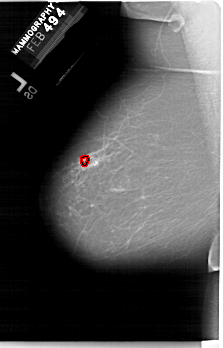

FILE: A_1275_1.LEFT_MLO.OVERLAY

TOTAL_ABNORMALITIES 1

ABNORMALITY 1

LESION_TYPE CALCIFICATION TYPE PLEOMORPHIC DISTRIBUTION CLUSTERED

ASSESSMENT 4

SUBTLETY 3

PATHOLOGY BENIGN

TOTAL_OUTLINES 1

BOUNDARY